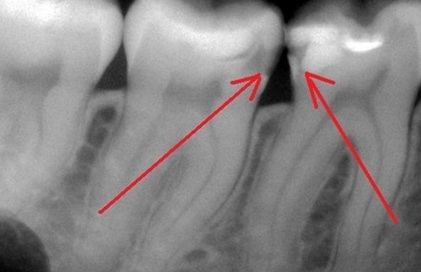

Я это к тому, что своим пациентам я всегда указываю на маленькие дырочки. До превращения такой дырочки в пульпит, когда нужно удалять нерв, по моим наблюдениям проходит шесть лет.